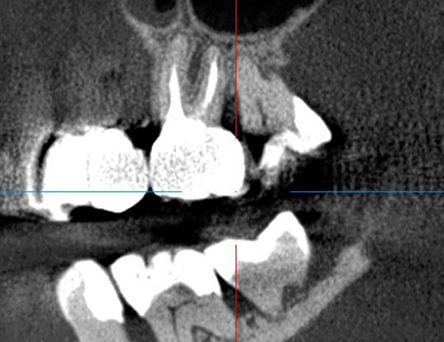

Проблема: У пациента отек щеки, боли самопроизвольные, усиливающиеся при приеме пищи, неудачное первичное лечение зуба (старыми методами).

Лечение: Проведено эндодонтическое перелечивание зуба под дентальным микроскопом, что позволило точно выявить анатомические особенности корневых каналов и устранить последствия ранее некачественного лечения. После купирования воспалительного процесса (киста) каналы герметично запломбированы. Коронковая часть зуба восстановлена для сохранения функции и герметичности до этапа постоянного протезирования.